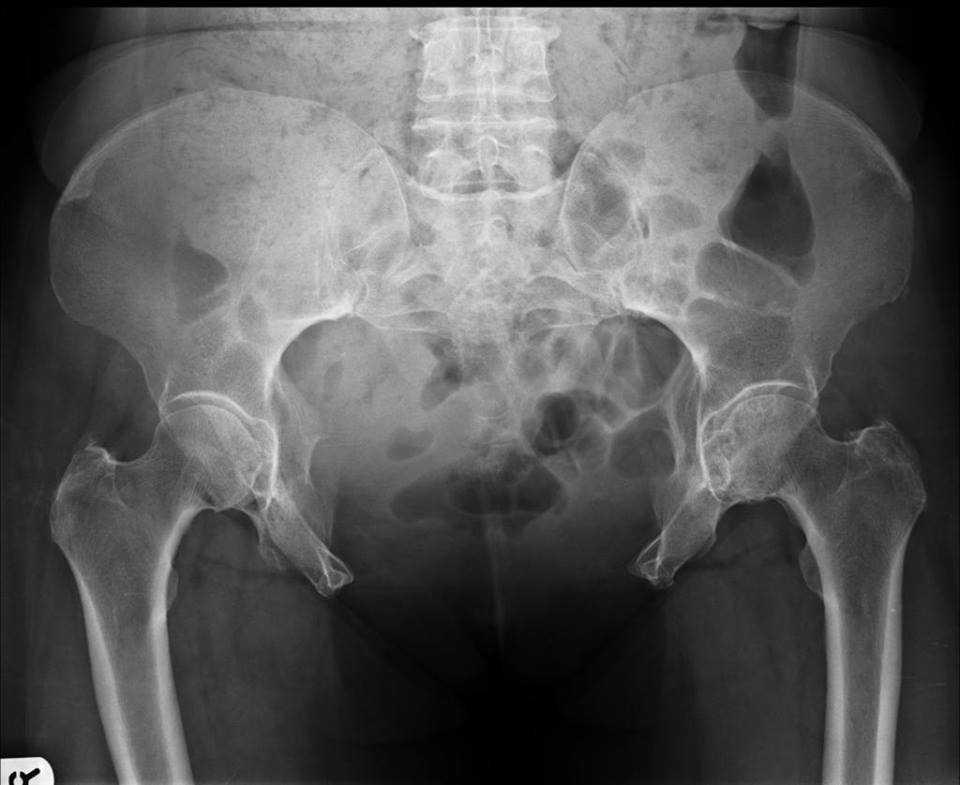

Q: Something fishy going on here. What's it called? ANSWER: https://goo.gl/16XMPC

#FOAMrad#FOAMed pic.twitter.com/o1rVrjGo9T